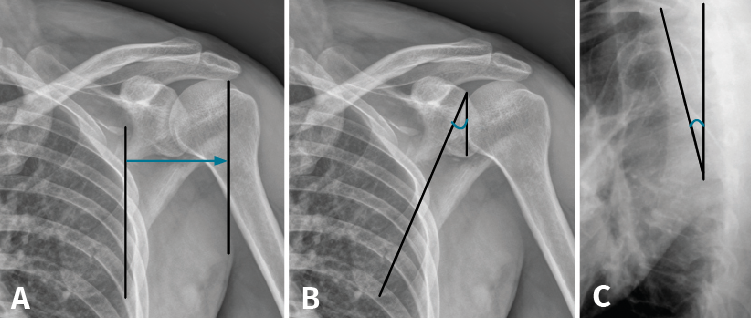

Tras la realización del estudio de imagen obtuvimos unas medidas de 64 mm para el offset del borde lateral, un ángulo glenopolar de 27,5°, una angulación de la deformidad correspondiente a 12,9° (Figura 6) y, por último, una superficie articular conservada íntegramente, visualizada en los cortes y en la reconstrucción tridimensional de la TC.

Figura 6. A: offset del borde lateral; B: ángulo glenopolar; C: angulación de la deformidad.